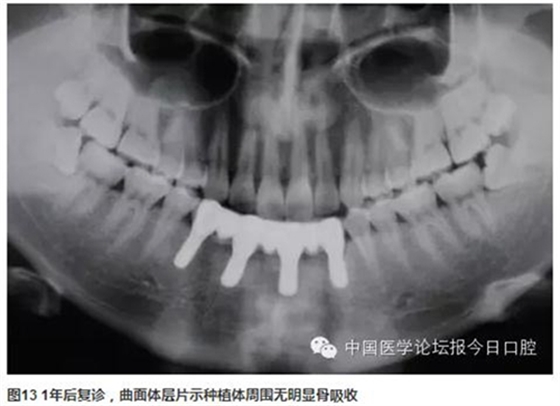

曲面體層片示:種植體基臺(tái)與修復(fù)體密合性良好。1年后復(fù)診,支架無(wú)松動(dòng)、折斷,中央螺絲未見(jiàn)折斷、松動(dòng),修復(fù)體未見(jiàn)崩瓷。種植體無(wú)松動(dòng),種植體周圍少量軟垢存,黏膜未見(jiàn)紅腫。種植體周圍探診深度:下頜左側(cè)尖牙(近中2mm、頰側(cè)3mm、遠(yuǎn)中4mm、舌側(cè)2mm),下頜左側(cè)中切牙(近中2mm、頰側(cè)2mm、遠(yuǎn)中4mm、舌側(cè)2mm),下頜右側(cè)側(cè)切牙(近中2mm、頰側(cè)2mm、遠(yuǎn)中3mm、舌側(cè)3mm),下頜右側(cè)第一前磨牙(近中3mm、頰側(cè)2mm、遠(yuǎn)中4mm、舌側(cè)3mm)(圖11~圖13)。